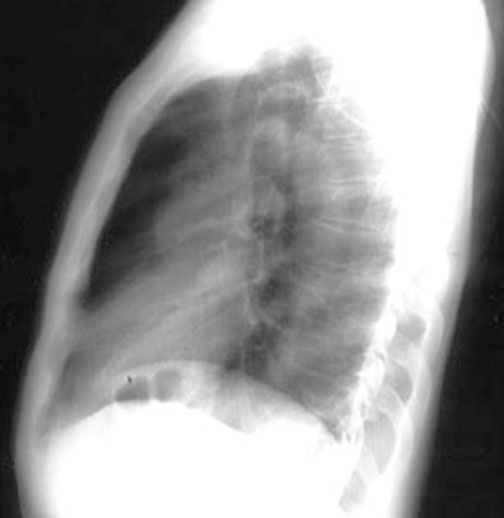

Lateral